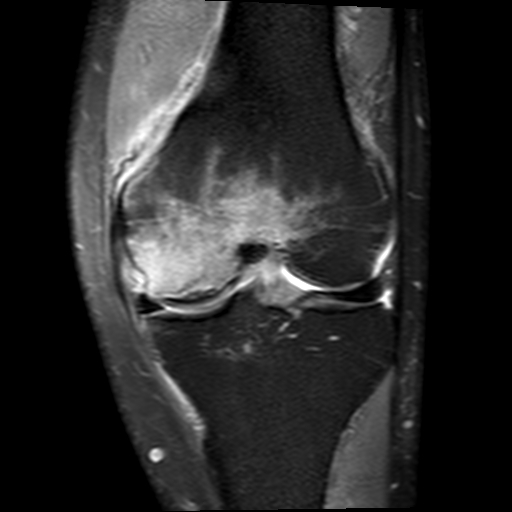

Segond fracture

Dr Subhan Iqbal◉ and Assoc Prof Frank Gaillard◉◈ et al.

Segond fracture is an avulsion fracture of the knee that involves the lateral aspect of the tibial plateau and is very frequently (~75% of cases) associated with disruption of the anterior cruciate ligament (ACL). On the frontal knee radiograph, it may be referred to as the lateral capsular sign.

MRI

MRI is essential in all cases of Segond fractures to identify internal derangement. Disruption of the ACL is the most common, however, there are additional frequently encountered injuries.

Associated injuries include 1,3:

ACL tear

most common associated injury

75-100% of cases 6

medial or lateral meniscal tear

66-75% of cases 6

posterior horn most common

avulsion of ACL from the tibial attachment: rare

avulsion of fibular attachment of the long head of biceps femoris

avulsion of the fibular collateral ligament